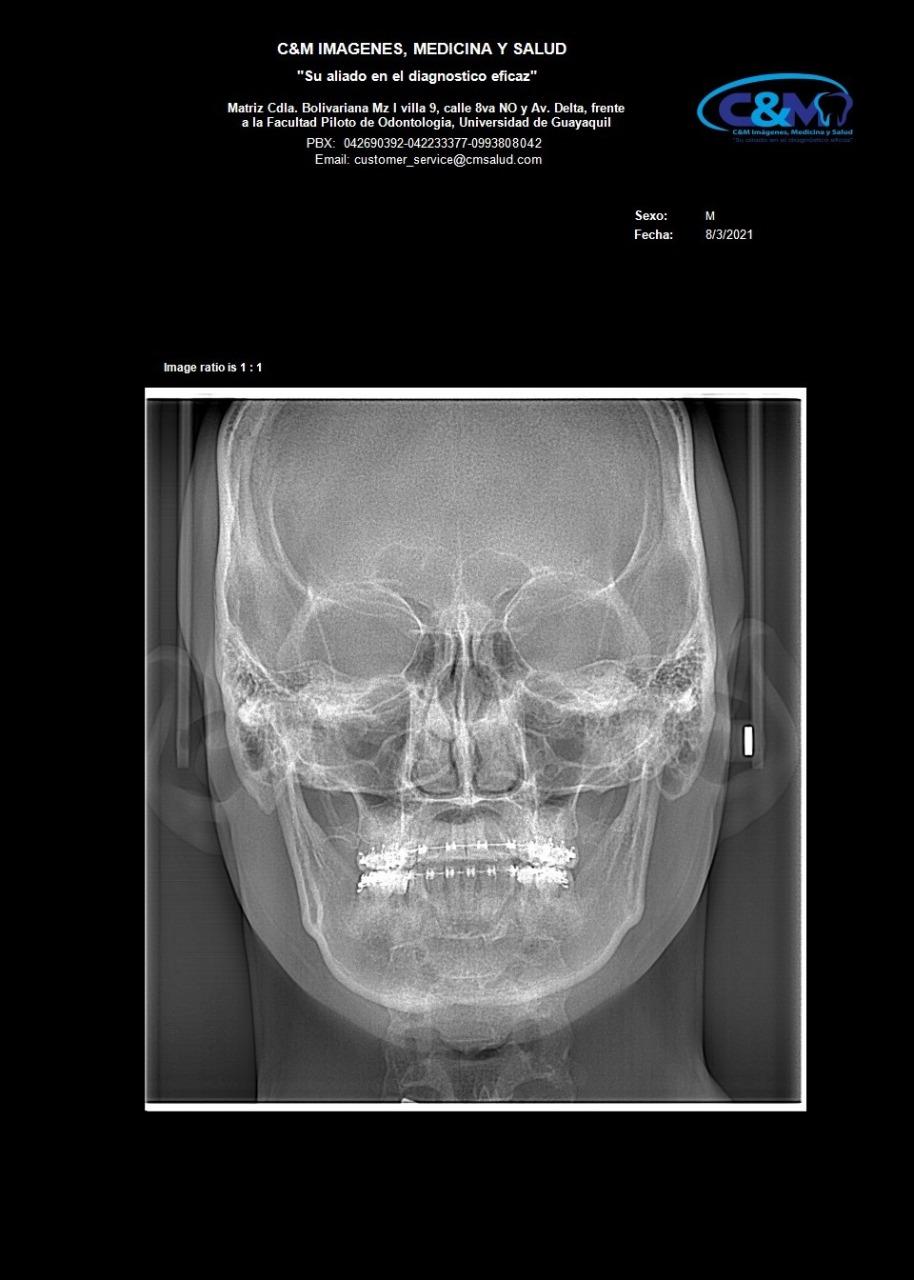

ANTEROPOSTERIOR